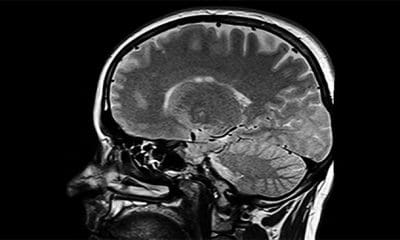

Una mujer estadounidense de 26 años se sometió a una operación que le extirparan un supuesto tumor que tenía en el cerebro. Sin embargo, la sorpresa...